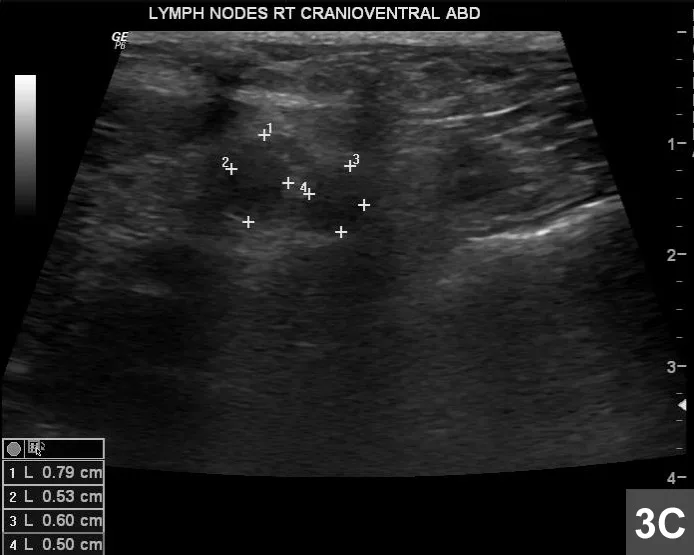

Figure 3C

Paired hypoechoic lymph nodes in the right cranioventral abdomen (+ markers) are enlarged.

Pancreatic neoplasia was suspected based on a focal abnormal region with mineralization; its location in the right lobe was likely causing the CBD obstruction. Paired hypoechoic regional lymph nodes in the right cranioventral abdomen measuring 0.79 × 0.53 cm and 0.60 × 0.50 cm (Figure 3C) were suspected to be reactive or secondary to metastatic neoplasia. The remaining viscera were otherwise normal; no foreign body or other GI abnormality was detected, nor was free fluid.